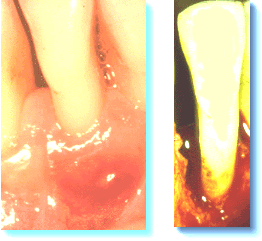

Mujer de 45 años de edad, que se queja de dolor a las 3 semanas después del raspado y alisado radicular. Ella ha mantenido una buena  higiene oral en relación con el tratamiento. El margen  gingival había sanado y el tejido se adaptó  estrechamente a la supericie dental en la región coronal.  Se observa una fístula como resultado de un absceso periodontal.  El diagnóstico clínico de absceso periodontal era basado en el siguiente criterio:

A veces el drenaje de pús no puede obtenerse a través de la bolsa periodontal y es necesario realizar un drenaje quirúrgico.  La imagen de la derecha se obtuvo en la cirugía  y la causa del absceso puede identificarse claramente. Es importante intentar tratar la condición lo más pronto posible. Debe eliminar el cemento infectado, cálculo y placa bacteriana, de lo contrario el proceso continuará destruyendo tejido óseo y periodontal